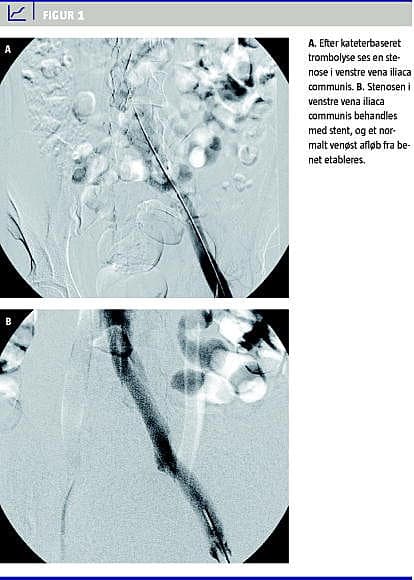

Anlæggelse af et trombolysekateter foregår på Billeddiagnostisk Afdeling. Kateteret (med multiple sidehuller) anlægges i lokal analgesi via vena poplitea under gennemlysning og føres antegradt ind i det tromboserede venesegment op til vena iliaca communis på overgangen til den nedre del af vena cava inferior. Kateteret kobles til en infusionspumpe, hvorefter det trombolytiske agens og heparin opblandet i isotonisk saltvand infunderes ved såkaldt pulse spray -infusion i et volumen på 120 ml pr. time. Der foretages dagligt kontrolflebografi til vurdering af behandlingseffekten. Når trombemasserne er opløst (efter 2-3 dages behandling), foretages stentning af eventuel iliacastenose (Figur 1 A og B), og herefter seponeres trombolysekateteret under dække af lavmolekylært heparin. Under behandlingen er patienten sengeliggende og udstyret med en sequentiel compression device for at øge det venøse flow gennem det behandlede venesegment og dermed hindre retrombosering.

Størstedelen af patienterne har venstresidig DVT som følge af iliacakompressionssyndrom og stenose, hvor den venstre vena iliaca communis komprimeres mellem den overkrydsende højre arteria iliaca communis og femte lændehvirvel bagtil, kendt som May-Thurner syndrom [13]. I forbindelse med trombolysebehandlingen er det muligt at behandle denne tilgrundliggende stenose med stentanlæggelse. I nogle studier er frekvensen af stentbehandling 20-40%, mens den i andre studier er op mod 70-80%.